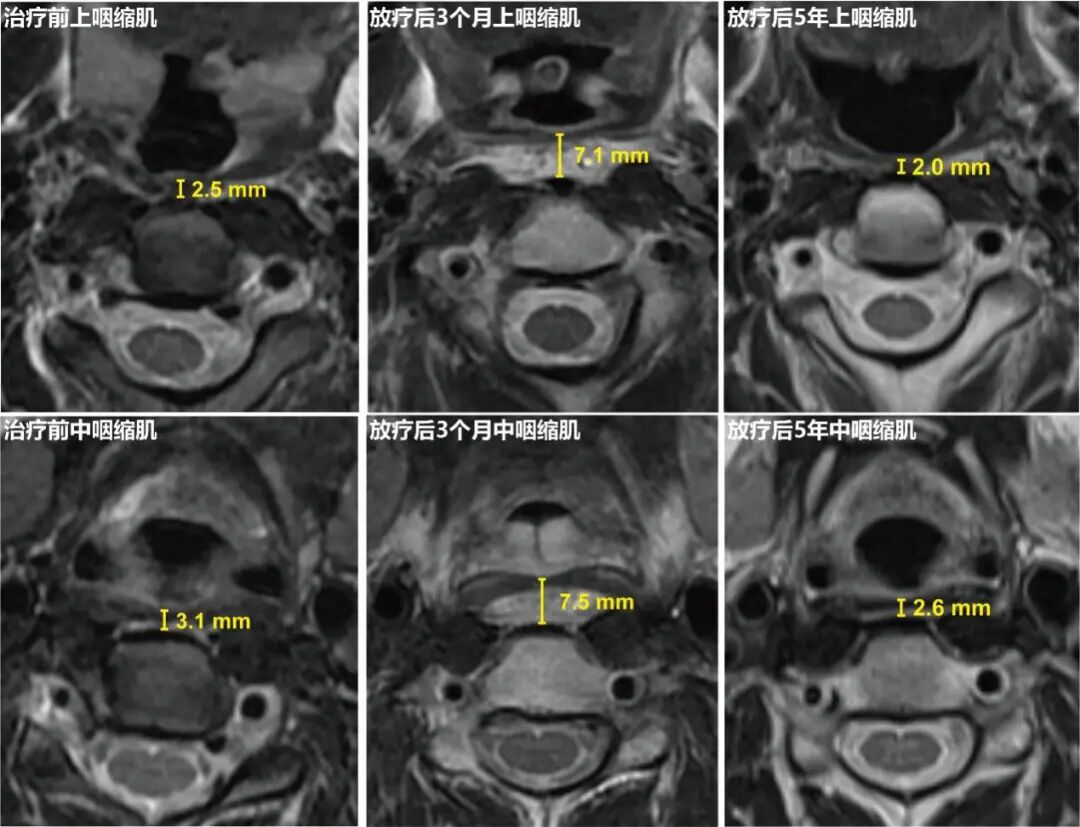

“内侧组咽后区豁免放疗”将咽缩肌接受>50Gy剂量的照射体积百分比由标准组的63%大幅降至8%。这种剂量学的优化转化为了明确的组织病理学获益。基于MRI的咽缩肌厚度动态测量结果显示,对比标准放疗组,内侧组咽后区豁免放疗组中,上咽缩肌和中咽缩肌早期水肿程度和晚期萎缩程度均明显减轻,具体表现为:放疗后3个月上咽缩肌(4.96 对比 5.09 mm, P=0.04)和中咽缩肌(5.39 对比 5.56 mm, P=0.03)的平均厚度更薄,以及放疗后5年上咽缩肌(1.80 对比 1.65 mm, P=0.005)和咽中缩肌(2.34 对比 2.15 mm, P=0.01)平均厚度更厚。

图3:治疗前、放疗后3个月及放疗后5年的上咽缩肌和中咽缩肌厚度